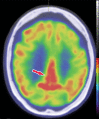

Neurodegenerative diseases are a devastating group of disorders that can be difficult to accurately diagnose. Although these disorders are difficult to manage owing to relatively limited treatment options, an early and correct diagnosis can help with managing symptoms and coping with the later stages of these disease processes. Both anatomic structural imaging and physiologic molecular imaging have evolved to a state in which these neurodegenerative processes can be identified relatively early with high accuracy. To determine the underlying disease, the radiologist should understand the different distributions and pathophysiologic processes involved. High-spatial-resolution MRI allows detection of subtle morphologic changes, as well as potential complications and alternate diagnoses, while molecular imaging allows visualization of altered function or abnormal increased or decreased concentration of disease-specific markers. These methodologies are complementary. Appropriate workup and interpretation of diagnostic studies require an integrated, multimodality, multidisciplinary approach. This article reviews the protocols and findings at MRI and nuclear medicine imaging, including with the use of flurodeoxyglucose, amyloid tracers, and dopaminergic transporter imaging (ioflupane). The pathophysiology of some of the major neurodegenerative processes and their clinical presentations are also reviewed; this information is critical to understand how these imaging modalities work, and it aids in the integration of clinical data to help synthesize a final diagnosis. Radiologists and nuclear medicine physicians aiming to include the evaluation of neurodegenerative diseases in their practice should be aware of and familiar with the multiple imaging modalities available and how using these modalities is essential in the multidisciplinary management of patients with neurodegenerative diseases.©RSNA, 2020.